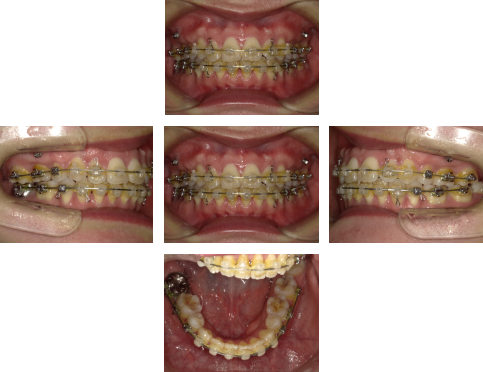

【治療中】

上顎左右4番、下顎左右5番の計4本を抜歯をし移動させるスペースを確保したあと、アンカースクリュー(水色の◯の箇所)を併用し、前歯を後方へ移動させました。

※関連記事:アンカースクリュー特集>>